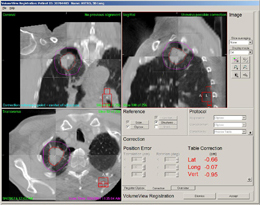

XVIは,2D単撮影モード(PlanarView™)や2D連続(透視)撮影モード(MotionView™)だけでなく,コーンビームCT技術による3Dボリューム撮影モード(VolumeView™)も備えており,これによって臨床情報も含めた位置合わせをサポートします(図1〜3)。従来のリニアックグラフィやポータルイメージング画像では確認することが困難であった軟部組織まで判別できるため,より正確な位置決めが可能になり,Elekta Synergy®での強度変調放射線治療(IMRT)や定位放射線治療(SRT)などの高精度な照射の実現に役立ちます。

![]() 図2 VolumeViewの画面(肺がん) |